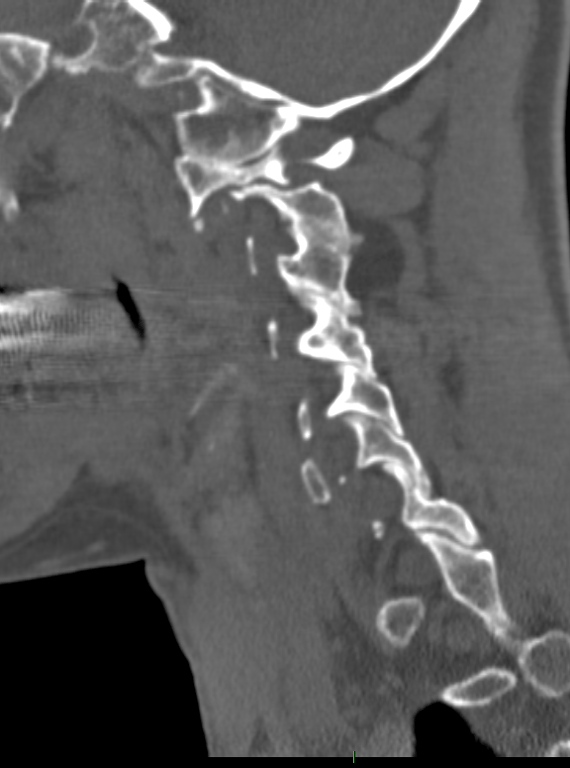

Sagittal CT shows extreme platybasia (NTB angle=180°), short clivus (<1.5 cm) and forward folding of the clivus–axis angle of Wackenheim (80°), causing lordotic tilt of the foramen magnum plane and plane of the occipital condyles, resulting in a retroflexed dens and severe basilar impression.

• Note violation of McGregor’s, Chamberlain’s and McRae’s lines by the dens. Also, extreme invagination of the opisthion (O) and high posterior C1 arch (C1).

• Sagittal MR shows distortion and compression of brainstem by both the dens and the opisthion